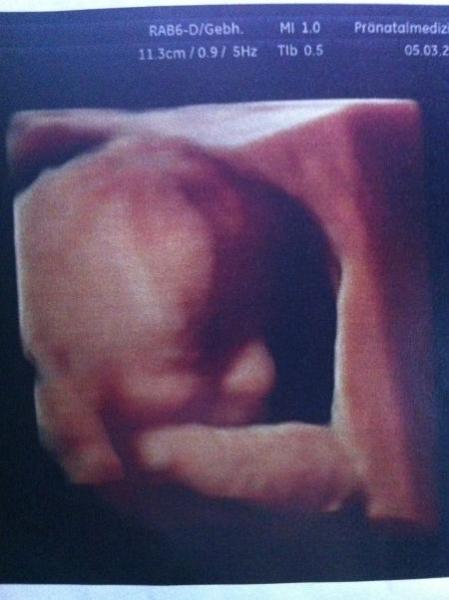

Hallo Mädels, ich bin jeden Tag bei euch nur fehlt mir grad im Alltagswahnsinn die Zeit zum schreiben. Aber heute hatte ich ein soo tolles Erlebnis. Letzte Woche bei der Vorsorge sagte mein FA das die Masse der Oberschenkel und des Kopfes passen würden aber die des Bäuchleins um 3 WOchen zurück lägen. Daraufhin bin ich heute auf eigene Faust zu meinem Prenataldignostiker der auch der Meinung das sie hinterher hinkt aber er meinte nur 1-1,5 Wochen und das sie eben kein Riese wird. Was nach wie vor ist das ich in der linken uterina einen leichten WIderstand habe der das Wachstum beeinflussen kann. Daraufhin bin ich zu meinem Gyn und habe ihn gebeten doch jetzt von 4 Wochen Abständen auf 2 Wochen Abstände zu gehen einfach weil ich Angst habe und er stimmte zu. Was aber ganz toll war heute ist , ich hatte ja diese Bauchdeckenstraffung und noch nie , bei keinem meiner 8 Kids habe ich ein 3 D Bild bekommen . Erst gab es das nicht und dann hatte ich die Narben. Heute hat bevor der Doc kam erst die Schwester vermessen und auf einmal schaltet die auf 3 D. Ich war zu Tränen gerührt. Und dann kam nochmal ein ganz anderes Bild wo sie mir erklärte das das der allerneuste 3 D wäre den sie noch nicht probiert hätte und ich wäre ihr Versuchtsobjekt. Wahnsinnsfotos.......... ich könnte die kleine Maus jetzt schon knutschen Ich hänge sie euch mal an....so ein tolles Erlebnis....für mich...denn Mausi hatte einmal einen Arm, dann den Zweiten Arm und dann beide Arme vorm Gesicht. Dann hat sie den Bauch eingezogen beim Messen (typisch Weib) und dann hat sie uns die Zunge rausgestreckt aber das wollte sie net als Photo drucken weil sie meinte da bekämen die Geschwister ja Angst. Sorry jetzt isses so lang, aber dafür schreib ich ja nicht so oft :-) Ich wünsch euch allen einen tollen Abend Drücklerle Nicole mit den 8 Kids und Laylani inside

Bild zu Auch mal wieder was von mir - Forum für Juni - Mamis